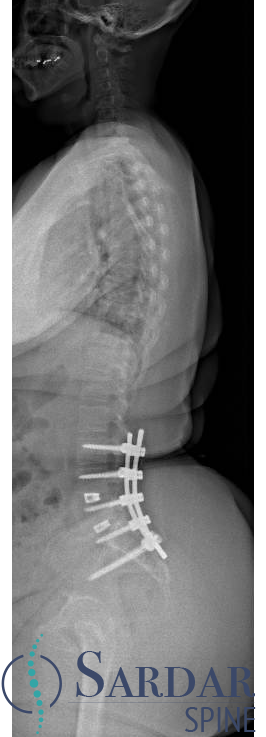

Severe malalignment case: Performed T12-S1/Pelvis posterior instrumentation, TLIF at L5-S1 & L5 PSO. No anterior approach on vascular team's advice. Patient now stands upright & grateful. #SpineSurgery #MedTwitter #scoliosis #flatback #HarringtonRods #ScoliosisWarrior

50s patient with severe malalignment. How would you treat this surgically? Nnee compensation in coronal and sagittal planes. Options: Multisegment instrumentation, TLIF/ALIF/OLIF, PSO, refer to another surgeon? Thoughts? #neurosurgery #spine #scoliosis #flatback #harringtonrods